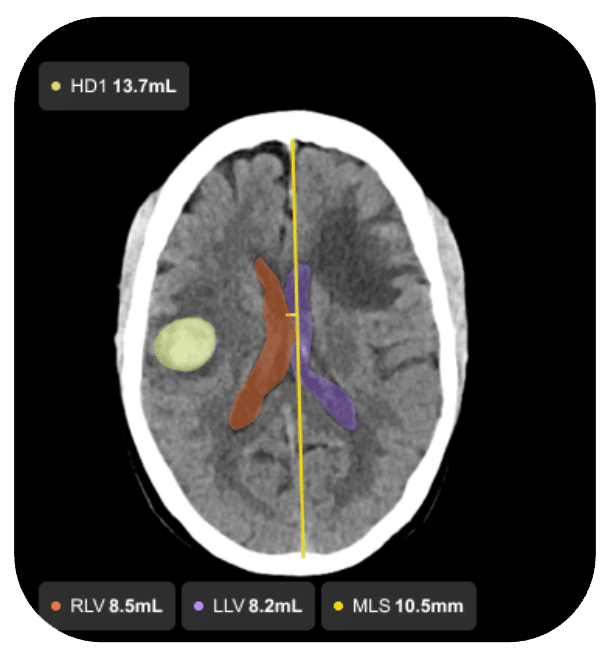

Intracranial Hemorrhage

• Automatically detects suspected intracranial hemorrhage (ICH), including subdural hematoma (SDH)

• Delivers consistent automated measurements, including volume, thickness, and midline shift

• Supports faster assessment and documentation